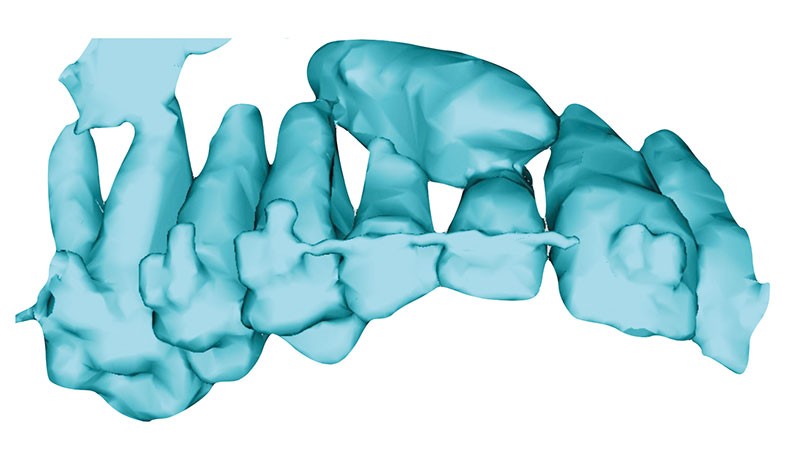

La reconstruction 3D confirme la position vestibulaire de la 13 avec appui coronaire sur la racine de 12 (fig. 8 et 9).